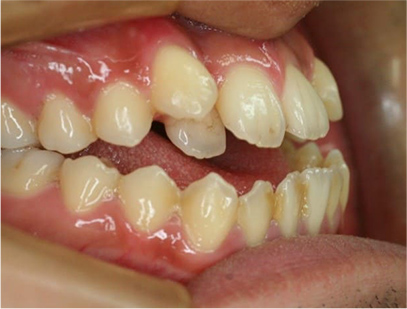

前歯が咬み合ってなく開咬の症例

上下の前歯が咬んでない事と前歯のデコボコを主訴として来院されました。

通常通り検査を行い「前歯部にデコボコを伴う開咬」と診断されました。

• 右側

• 左側